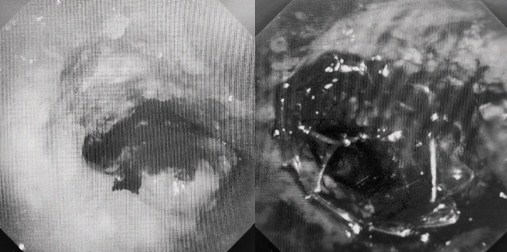

患者入院第二天,在麻醉手術(shù)中心全力配合下,歐陽海峰帶領(lǐng)呼吸介入團(tuán)隊(duì),歷時40分鐘快速置入硬質(zhì)支氣管鏡、鏟切腫瘤,并順利植入全覆膜TTS支氣管金屬支架。患者氣短癥狀即刻緩解,為患者贏得了寶貴的后續(xù)治療機(jī)會。